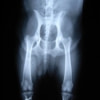

■ 症例24 キャバリア 7か月

左右膝蓋骨内方脱臼(左:グレードⅣ 右:グレードⅢ)

以前から左右後肢の跛行が認められ、整形外科学的検査・レントゲン検査により左右の膝蓋骨脱臼が認められた。症状が重度である左膝の膝蓋骨脱臼整復術を行った。外科手技は縫工筋及び内側広筋の解放、脛骨粗面の外側転位、滑車ブロック形造溝術、内外側関節方の縫縮を実施した。術後一か月時点で、左の膝蓋骨は安定しており経過は良好である。

本症例は成長期における重度の膝蓋骨脱臼であり、術後の再発の可能性もあるため、経過をしっかりと観察していく必要がある。また、今回手術を実施していない右膝に関しても経過を観察し、手術を検討していくこととする。